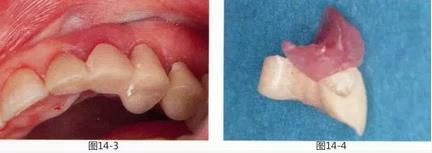

圖12-1   26歲,女性。由其他診所介紹而來。右上橋體部的基底容易滯留食物殘渣。

圖12-2  在形成唇側齦瓣時,發(fā)現(xiàn)右上2根尖對應位置有牙間囊腫造成的牙槽骨缺失。